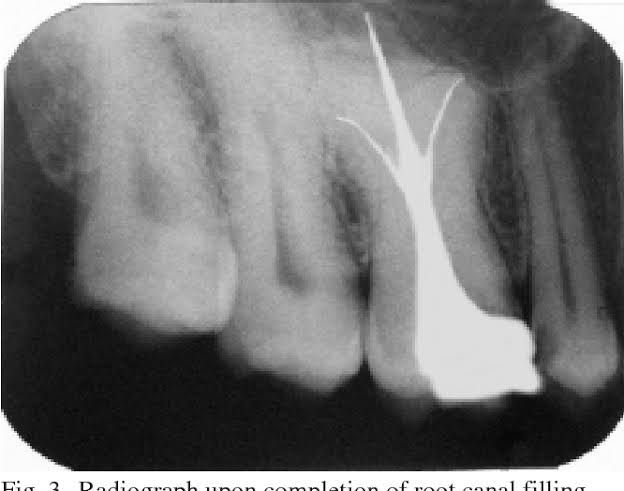

Taurodontism is a developmental disturbance of a tooth in which body is enlarged at the expense of the roots. An enlarged pulp chamber, apical displacement of the pulpal floor and lack of constriction at the cementoenamel junction are the characteristic features.